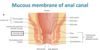

The anal canal is surrounded by what 3 things?

- Internal anal sphincter (smooth muscle)

- External anal sphincter (skeletal muscle)

- Fat of the ischioanal fossa